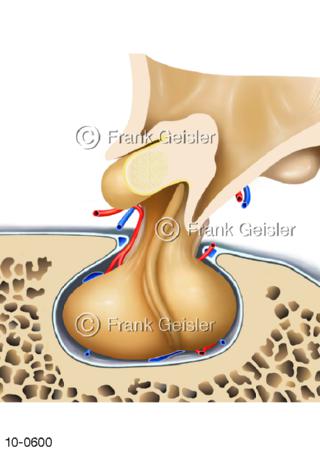

Bildergalerie Nervensystem

Bilder zum Nervensystem,dem Gehirn, Teil des zentralen Nervensystem, Zentralnervensystem ZNSmit Rückenmark, Abbildungen zum Nervengeflecht (Nervenplexus), die Verflechtungen von Nervenfasern, aus der Wirbelsäule hervortretende Nervenäst sowie Nervenzellen der Nerven